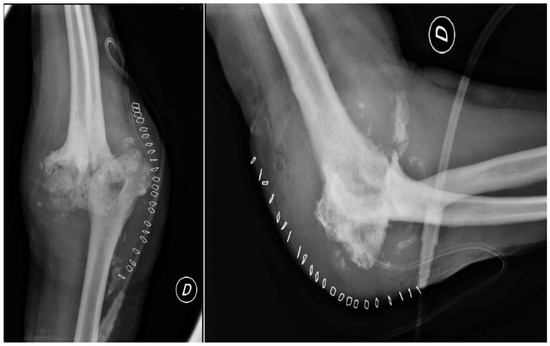

2.3. Further Investigations